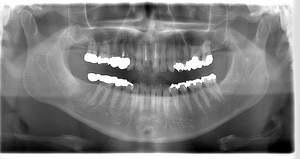

レントゲン写真

- Befor

- After

| 年齢 | 50代・男性 |

| 主訴 | 左上7番 左下5番7番 |

| 治療内容 | ・インプラント埋入 ※1:GBR(骨造成)・・・骨再生誘導法。骨の高さや厚みを人工骨や人工膜などを使用し再生する方法 |

| 治療費 | 合計:1,809,500円(税込) ■内訳 ・左上7番 ・左下5番7番 |

| 治療期間 | 左上7番約1年 左下5番7番約10ヵ月 |

| 治療方針 | 左上7番は昔他院で被せものをしており、被せものの中が歯ぐきの中まで虫歯になっていたため抜歯せざるを得ない状態だった。抜歯と同時に骨造成を行い、骨が出来るまで4ヵ月待ってからインプラントを埋入した。 ※2ポンティック・・・歯のない部分を補うダミーの歯。 |

| 担当者所見 | 元々金属の被せものが多く入っていたため、2次カリエス※3が多かった。今回は金属ではなく、ジルコニアを使用し、2次カリエスにならないよう、患者様にはブラッシング指導とメンテナンスの重要性をお伝えした。 ※3二次カリエス・・・詰め物や被せものを入れた歯が虫歯になること。 |